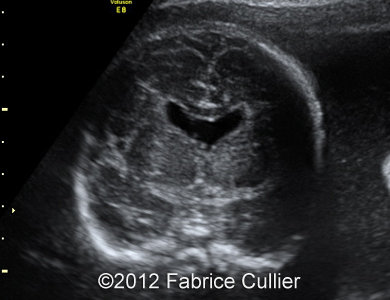

Images 1, 2: A transversal plane of the skull, too round (Brachycephaly).

1A

1B